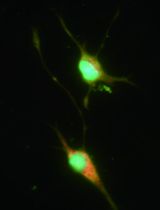

Atherosclerosis is a chronic inflammatory disease of the arterial wall characterized by lipid deposition, plaque formation, and immune cell infiltration. Innate and adaptive immune cells infiltrate the artery during development of the disease. Moreover, advanced disease leads to formation of artery tertiary lymphoid organs in the adventitia (Grabner et al., 2009; Hu et al., 2015). Various and diverse types of immune cells have been identified in the aorta adventitia vs atherosclerotic plaques (Elewa et al., 2016; Galkina et al., 2006; Lotzer et al., 2010; Mohanta et al., 2016; Mohanta et al., 2014; Moos et al., 2005; Srikakulapu et al., 2016; Zhao et al., 2004). There are conflicting reports on the number and subtypes of immune cells in the aorta depending on the age of the animals, the protocol that is used to obtain single cell suspensions, and the dietary conditions of the mice (Campbell et al., 2012; Clement et al., 2015; Galkina et al., 2006; Kyaw et al., 2012). The number of immune cells in the aorta differs as much as tenfold using different protocols (Butcher et al., 2012; Galkina et al., 2006; Gjurich et al., 2015; Grabner et al., 2009; Hu et al., 2015). These discrepant results call for a protocol that robustly documents bona fide aorta cells rather than those in the surrounding tissues or blood. Critical methodological hurdles include the removal of adjacent adipose tissue and small paraaortic lymph nodes lining the entire aortic tree that are not visible by the naked eye. A dissection microscope is therefore recommended. Moreover protocols of aorta preparations should ascertain that lymphocyte aggregates referred to as fat associated lymphoid clusters (FALCs) (Benezech et al., 2015; Elewa et al., 2015) that are often present at the border between the adipose tissue and the adventitia are removed before enzyme digestion. We propose - besides other approaches (Hu et al., 2015; Mohanta et al., 2014) - a combination of immunohistochemical staining and fluorescence activated cell sorter (FACS) analyses from single cell suspensions to quantify the cells of interest. This protocol describes isolation of single cells from mouse aorta for FACS and other analysis.